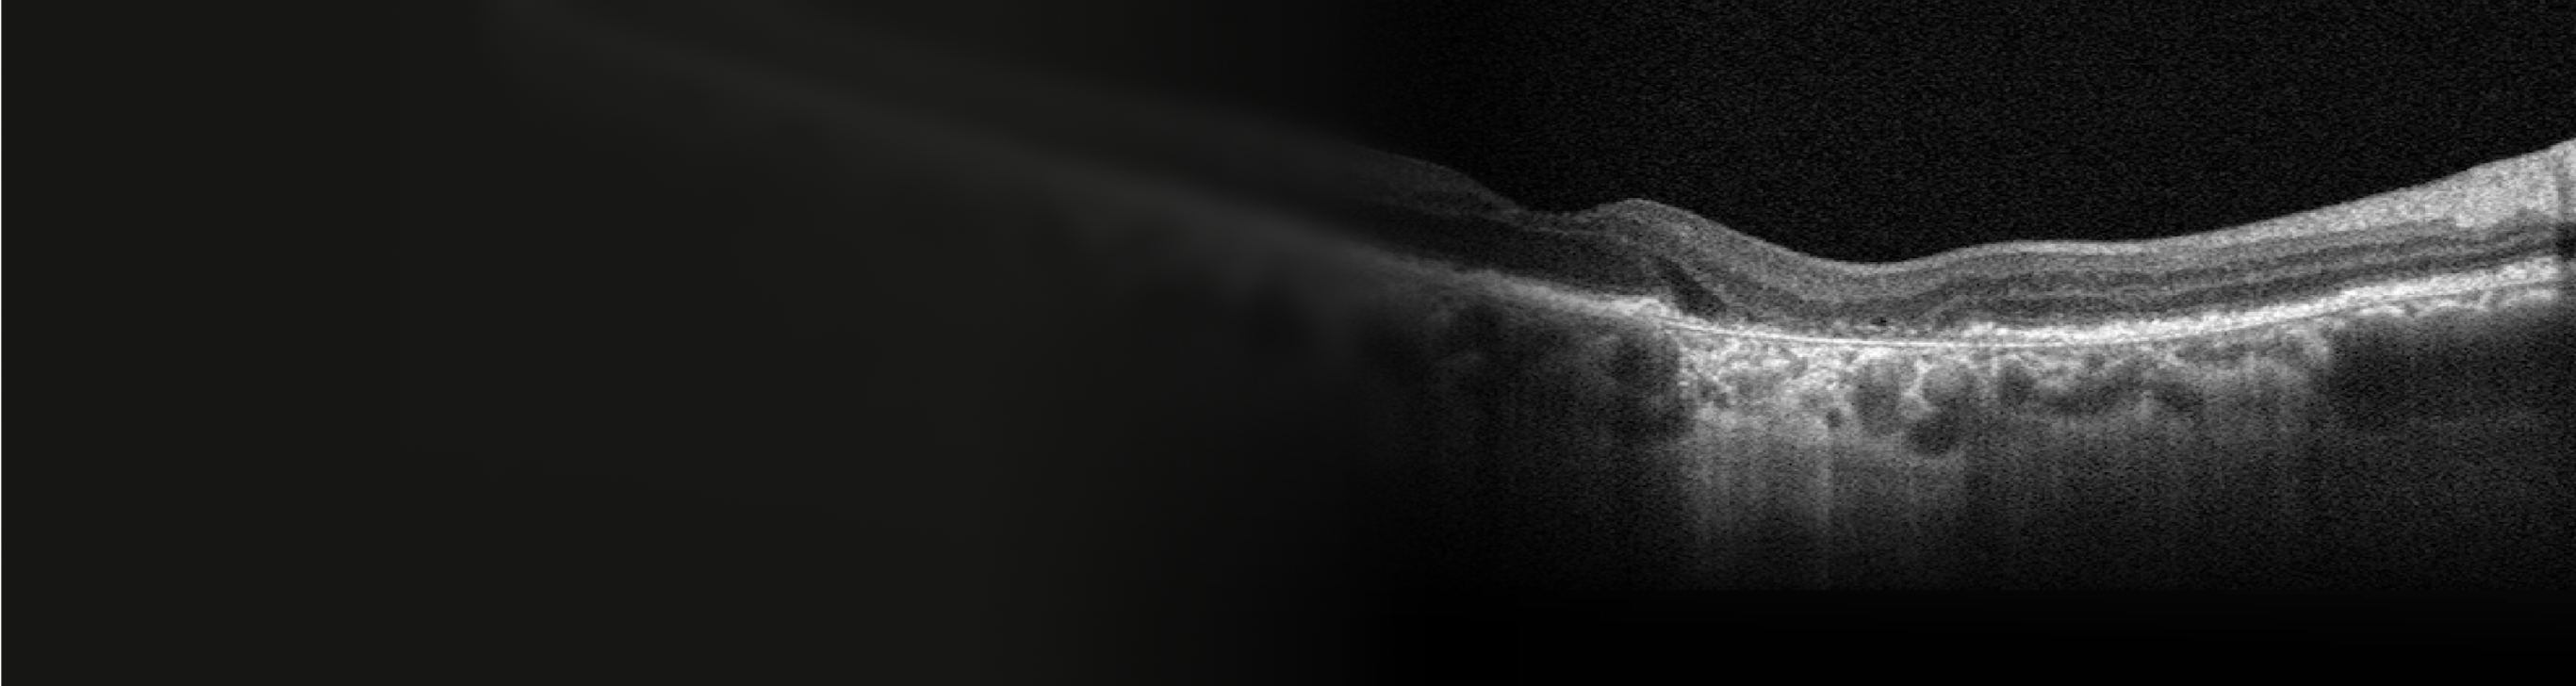

Year 4

BCVA: 6/15

Lesion has grown closer to the fovea as shown by larger area of hypertransmission on OCT. However, BCVA has only declined slightly as fovea is still intact.